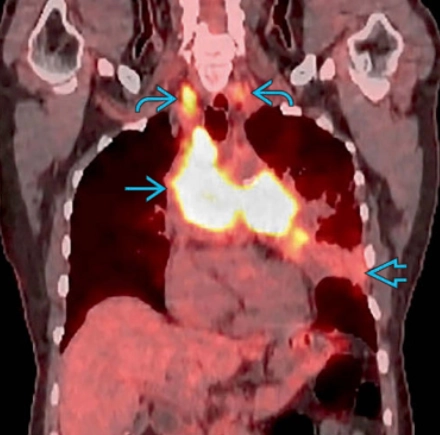

Bệnh phổi do xạ trị (Radiation-induced lung disease - RILD)

Bệnh phổi do thuốc (Drug-induced lung disease)